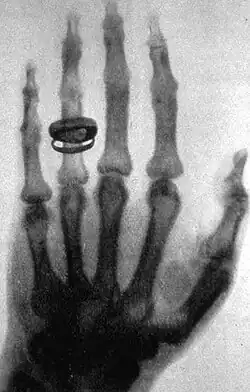

Um dos últimos objetos de estudo de Helmholtz foi o eletromagnetismo, sendo o primeiro a demonstrar a radiação eletromagnética, onde a posterior descoberta do raio-X pelo alemão Wilhelm Conrad Röntgen em 1895 está inserida. O achado rendeu-lhe o primeiro Prêmio Nobel de Física e abriu caminho para estudos que renderiam o terceiro prêmio, dado a Antoine Henri Becquerel, Pierre e Marie Curie pelas observações e interpretações de resultados sobre as emissões de partículas provenientes de corpos radioativos (radioatividade). Já em 1908, por formular hipóteses sobre substâncias radioativas, Ernest Rutherford foi laureado com o Nobel de Química.